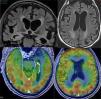

Dementia is a syndrome characterised by chronic, multi-domain, acquired cognitive impairment that causes significant functional limitations. MRI is the standard imaging study for these cases, since it enables detection of the atrophy patterns of the various neurodegenerative diseases (Alzheimer's disease, frontotemporal degeneration, Lewy body dementia), the vascular lesions associated with vascular dementia, and various potentially reversible diseases (for example, tumours, hydrocephaly) or diseases that require special management measures (for example, prion diseases). In certain cases other imaging methods can be used, such as CT, functional MRI, HMPAO SPECT or dopaminergic markers and FDG PET, amyloid markers or dopaminergic markers. The indications for these methods have not yet been clearly established, and therefore should be used in multidisciplinary dementia units.